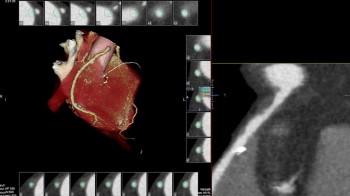

- MSCT koronarografija (prikaz krvnih žila srca CT-om, bez neugodnosti i komplikacija koje nosi klasična koronarografija), u saradnji s Poliklinkom dr.Al-Tawil